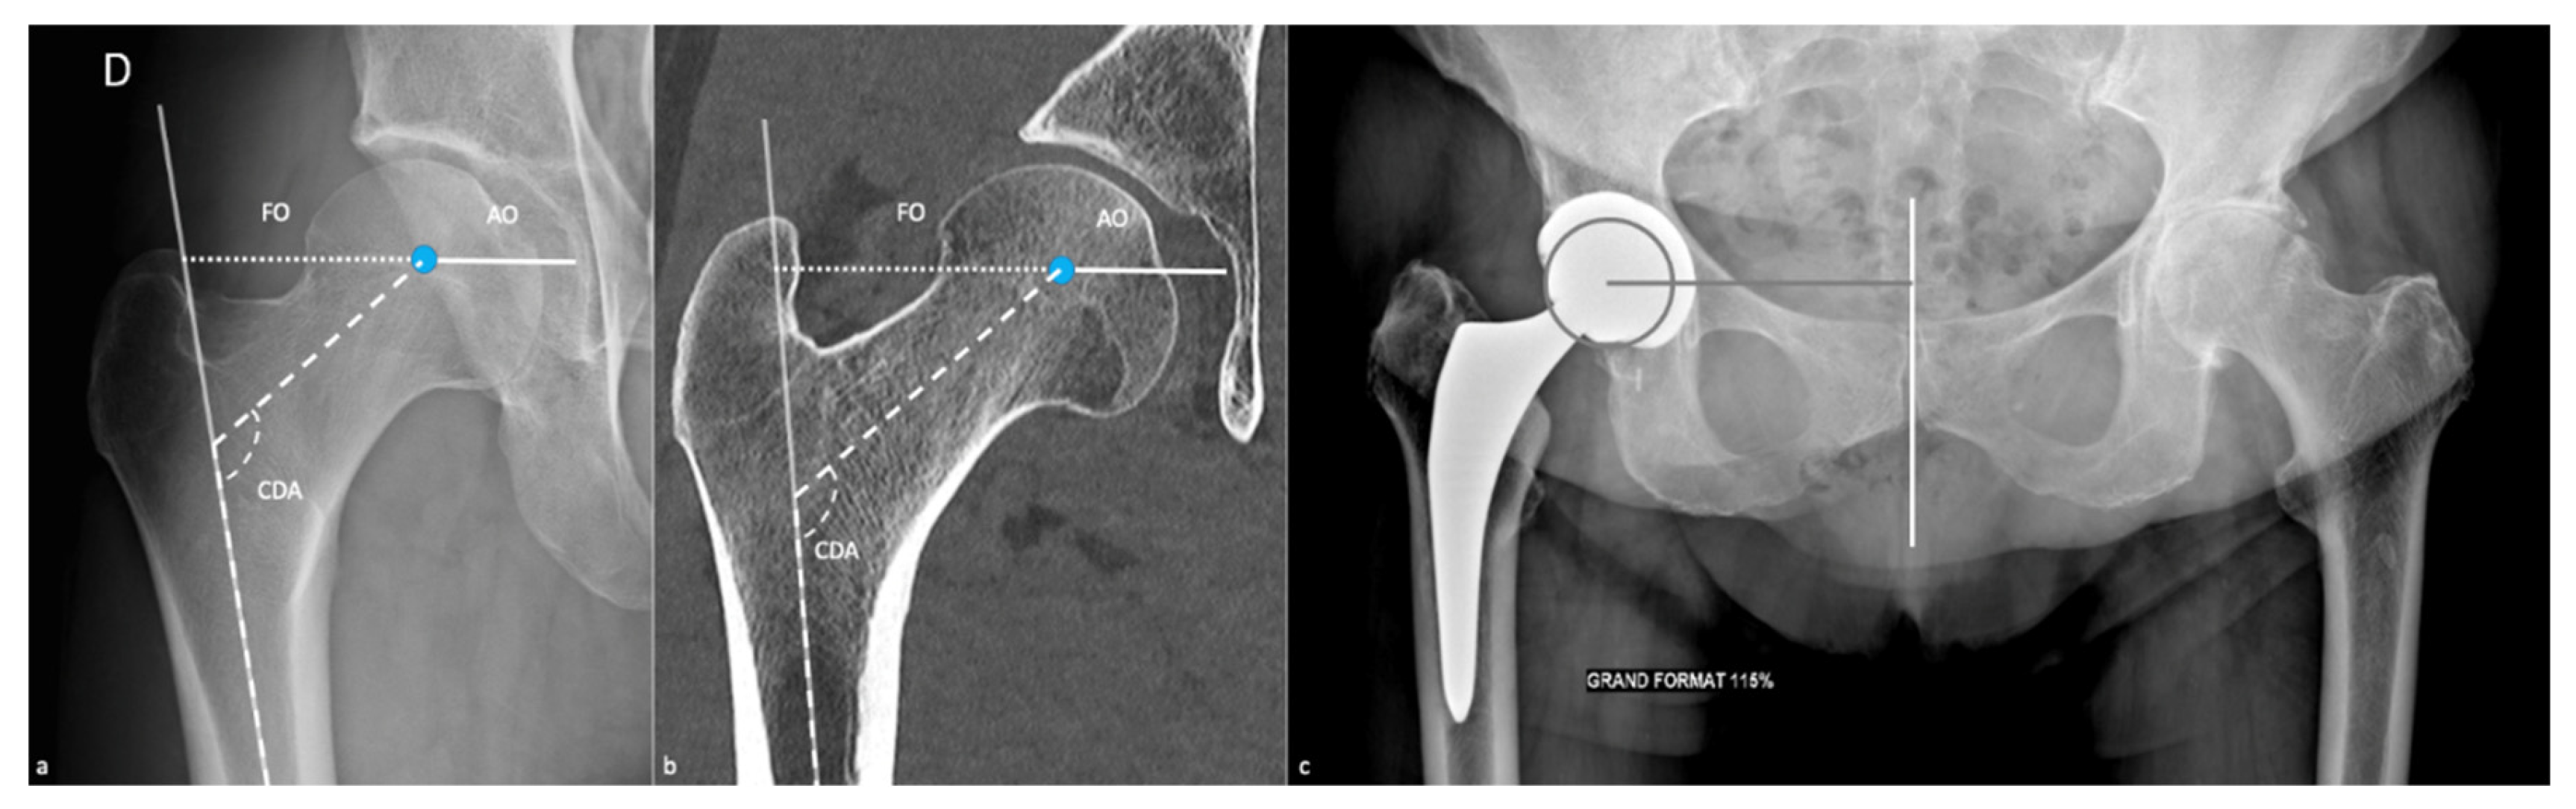

2.2.1. Measurements and Their Implications

| AO | acetabular offset |

| CDA | cervico-diaphyseal angle |

| FO | femoral offset |

| GO | global offset |